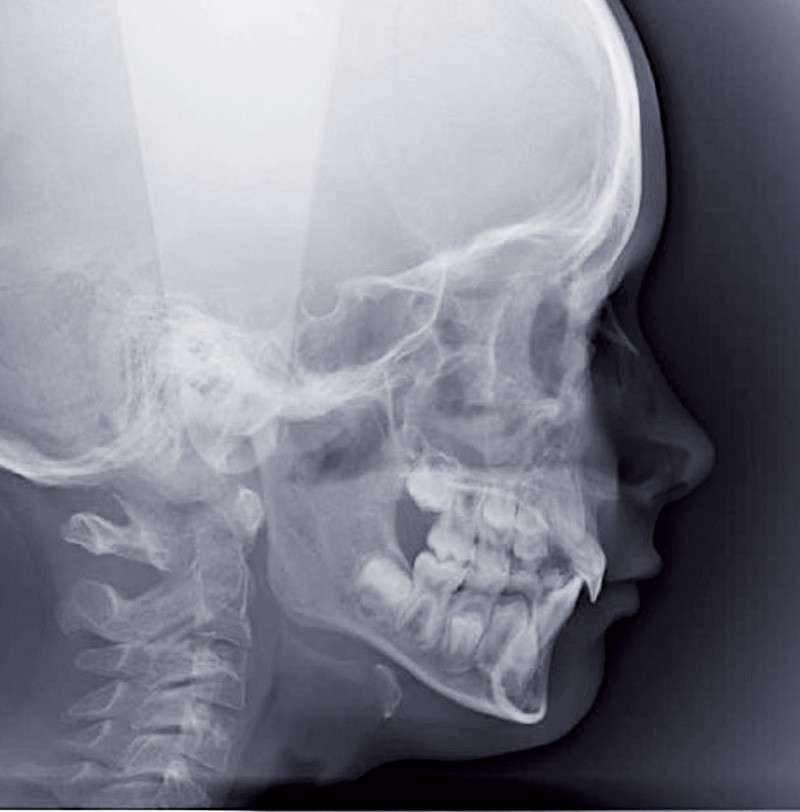

Le jeune Yoan 9 ans est adressé par son chirurgien maxillofacial, suite à l’exérèse d’un kyste bénin du maxillaire, et l’avulsion de 21 et 23 (fig. 1). L’apex de 22 a été soufflé par le kyste. La céphalométrie (fig. 2a et b) et l’examen clinique mettent en évidence une classe II squelettique par rétromandibulie, ainsi qu’une classe II dentaire. Le patient, est particulièrement perturbé par l’intervention qu’il vient de subir, et la coopération s’annonce difficile.